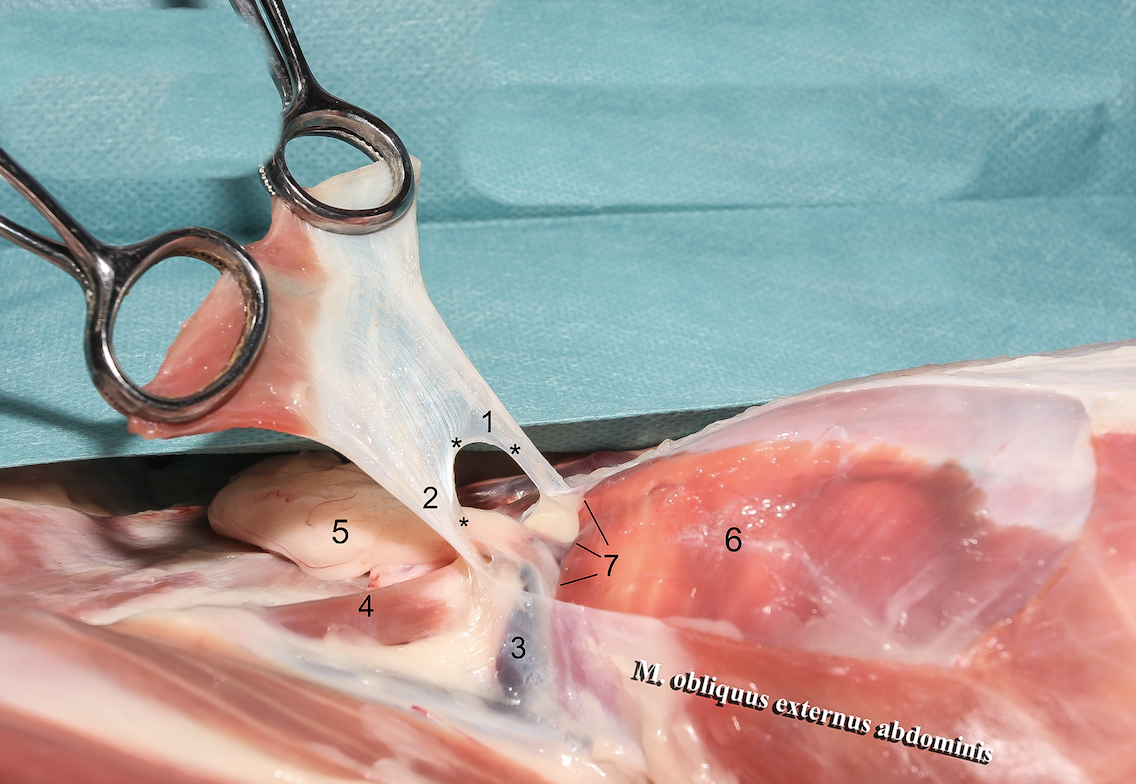

**Anulus inguinalis superficialis**

26

**M. obliquus internus abdominis**

27

**M. obliquus externus abdominis**

28

**Tunica vaginalis**

29

**Proc. vaginalis**

30

**Lig. teres uteri**